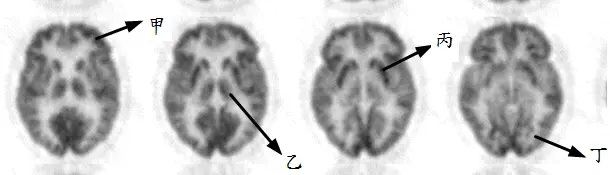

附圖為腦部 FDG-PET 影像,關於各部位的解剖位置名稱,下列敘述何者錯誤?

A甲-額葉( frontal lobe )

B乙-杏仁核( amygdaloid )

C丙-基底核( basal ganglia )

D丁-枕葉( occipital lobe )

影像呈現四張連續的腦部軸位(axial)FDG-PET 切面,由左至右為由淺入深的切面序列。各標記位置分析如下:

- 甲:標示於最左側(最上層)切面的前方皮質區。此位置位於大腦前方、頭頂方向,對應額葉(frontal lobe)。正常 FDG 攝取均勻分布於灰質皮層,此處顯示正常皮質代謝活性。

- 乙:標示於同一左側切面的較深部、偏內側下方位置,箭頭指向腦室周圍的內側結構。此位置解剖上對應**視丘(thalamus)**或更深部的基底核相關區域,而非杏仁核(amygdaloid)。

- 丙:標示於第三張切面的雙側高亮對稱結構,位於大腦深部中央偏側方,為 FDG 攝取最旺盛的區域,對應基底核(basal ganglia)(含尾狀核 caudate nucleus、殼核 putamen、蒼白球 globus pallidus)。

- 丁:標示於最右側(最低層)切面的後方皮質區,對應大腦最後方的**枕葉(oc